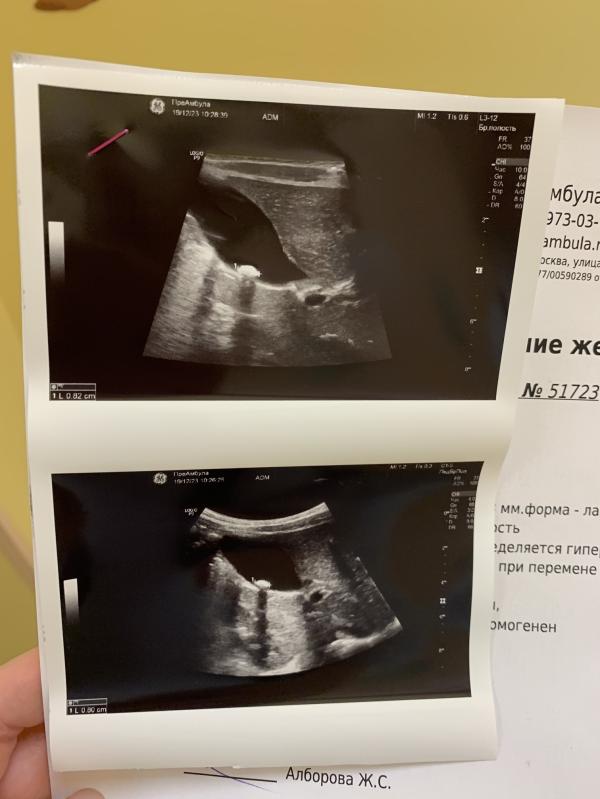

Камень в желчном у ребёнка

Здоровуууучий камень у Серёжи в желчном

Родился с таким

Камень в том же размере (8 мм)

Урсофальк пропивали неоднократно- камень не уменьшается! Но и не увеличивается. Тьфу тьфу!